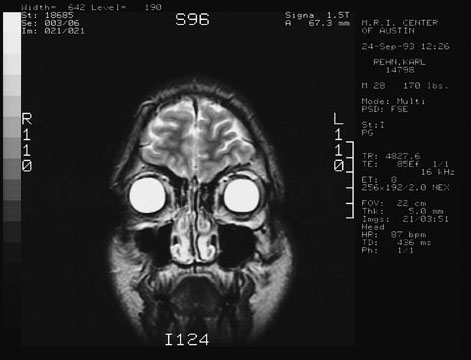

Here are 4 views taken from the MRI of my head.